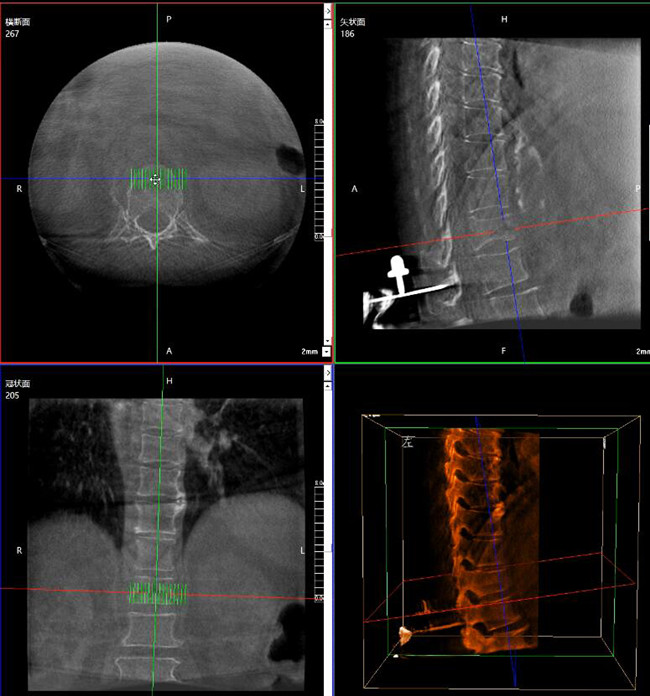

步骤一:C形臂三维重建+机器人手术规划

使用普爱医疗三维C形臂对患者进行胸椎影像扫描及三维重建,图像被同步传输到普爱医疗骨科机器人导航系统。

借助骨科机器人的规划软件进行术前手术路径模拟规划,找到穿刺位置和角度,操作机械臂快速完成手术入点的准确定位。

*术前规划